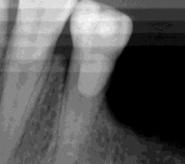

Las Figuras 1-3 muestran las imágenes de la cavidad bucal de la paciente. Se puede observar el deterioro generalizado de la salud bucodental, destacando la higiene dental deficiente, gingivitis, restauraciones dentales desajustadas, exposiciones radiculares, anodoncias parciales y caries radiogénica.

Las Figuras 4-13 son imágenes radiográficas de los dientes de la paciente que presen tan múltiples lesiones periapicales como consecuencia de las necrosis pulpares originadas por la radioterapia. Se realizaron los

tratamientos y retratamientos endodónticos necesarios para preservar los dientes en boca, evitando las exodoncias y por lo tanto minimizando el riesgo de generar osteorradionecrosis.